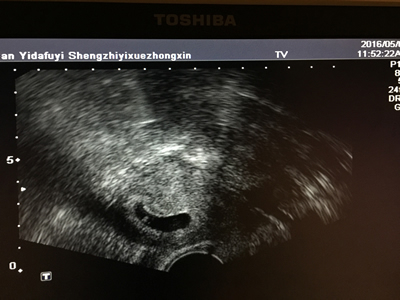

患者临床妊娠B超图像 患者移植后第10天B超内膜图像,内膜5.3mm

4月6日,陈女士怀着忐忑的心情接受了2枚冻胚解冻移植,10天后奇迹出现,其血、尿HCG呈阳性,提示生化妊娠。虽然在妊娠期间陈女士曾出现少量阴道出血,但经细致保胎措施,阴道流血很快消失。移植后近30天,B超显示宫内单胎妊娠,表明该女士临床妊娠成功。临床妊娠成功意味着生殖中心的任务已经完成,但因“成果”来之不易,妊娠后3个月是流产高危期,郭玉佳主任带领的团队仍继续对陈女士进行各方面的细心呵护和必要的妊娠支持,最终帮助其平安渡过该段危险期。目前患者已进入孕中期,处于稳定妊娠中,B超观察显示胎儿情况良好。